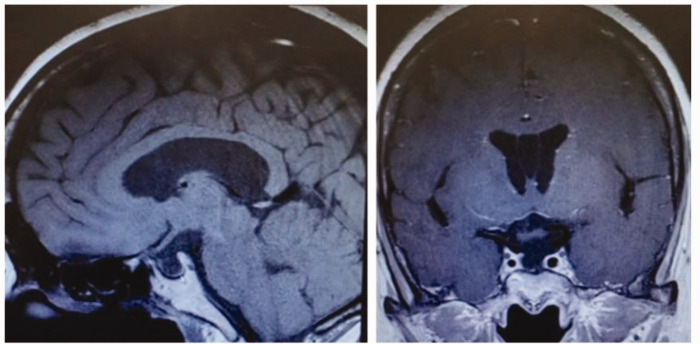

希恩综合征是一种由产后出血后垂体缺血性坏死引起的疾病,通常导致垂体功能障碍,可影响肾上腺、甲状腺和性腺轴。临床上,患者可表现为单轴或多轴功能障碍。希恩氏综合征和格雷夫斯病同时发生是极其罕见的,这给诊断带来了重大挑战。在此,我们报告一位50岁出头的女性,有28年的希恩综合征病史,导致完全的垂体功能障碍,在过去的20年里一直在治疗甲状腺功能减退。然而,在6个月的时间里,她出现慢性腹泻,并表现出进行性体重减轻,实验室结果显示甲状腺功能亢进。根据进一步的影像学和实验室检查结果,以及她的病史,根据促甲状腺激素受体抗体水平升高,诊断为希恩综合征合并格雷夫斯病。治疗包括促肾上腺皮质激素替代、抗甲状腺治疗和其他支持措施。虽然她的胃肠道症状和体重减轻最初得到解决,但在20个月的随访中,患者继续经历持续的甲状腺功能亢进和促甲状腺素受体抗体水平升高。本病例强调需要定期监测希恩综合征患者的内分泌,特别是那些长期甲状腺功能减退的患者,以及时识别和解决自身免疫性甲状腺疾病的潜在重叠。

Sheehan's syndrome is a disorder caused by ischemic necrosis of the pituitary gland following postpartum hemorrhage, typically resulting in pituitary dysfunction that can affect the adrenal, thyroid, and gonadal axes. Clinically, patients may present with dysfunction of a single axis or multiple axes. The co-occurrence of Sheehan's syndrome and Graves' disease is extremely rare, posing a significant diagnostic challenge. Herein, we report the case of a woman in her early 50s with a 28-year history of Sheehan's syndrome, which had led to complete pituitary dysfunction, who had been managing hypothyroidism for the past 20 years. However, over a 6-month period, she developed chronic diarrhea and showed progressive weight loss and laboratory results indicating hyperthyroidism. Based on further imaging and laboratory findings, along with her medical history, a diagnosis of Sheehan's syndrome complicated with Graves' disease was established, as evidenced by elevated levels of thyrotropin receptor antibodies. Treatment included adrenocorticotropic hormone replacement, antithyroid therapy, and other supportive measures. Although her gastrointestinal symptoms and weight loss resolved initially, the patient continued to experience persistent hyperthyroidism and elevated thyrotropin receptor antibody levels at the 20-month follow-up. This case highlights the need for regular endocrine monitoring in patients with Sheehan's syndrome, particularly those with long-standing hypothyroidism, to promptly identify and address the potential overlap of autoimmune thyroid diseases.